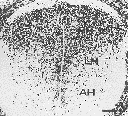

孕鼠于E10d腹腔注射BrdU,于胎鼠E17d时,脊髓上胸段BrdU免疫反应神经元主要集中在脊髓后角,脊髓侧角BrdU免疫反应神经元较少,前角仅有少量的BrdU免疫反应神经元(图1);孕鼠于E11d腹腔注射BrdU,于胎鼠E17d时,脊髓上胸段后角BrdU免疫反应神经元较E10d减少,侧角和前角BrdU免疫反应神经元较E10d增多(图2);孕鼠于E12d腹腔注射BrdU,于胎鼠E17d时,脊髓上胸段BrdU免疫反应神经元主要集中于前角和侧角,而后角仅有少量的BrdU免疫反应神经元(图3);孕鼠于E13、E14d腹腔注射BrdU,于胎鼠E17d时,脊髓上胸段未见BrdU免疫反应神经元出现。各例鼠胎脊髓的部分相邻切片以磷酸缓冲液替代抗BrdU第一抗体后未见BrdU免疫反应神经元(图4)。各实验组BrdU标记结果稳定,形态学变化基本一致。

图2 E11d腹腔注射BrdU,E17d脊髓上胸段后角(PH)BrdU免疫反应神经元较E10d减少,侧角(LH)和前角(AH)BrdU免疫反应神经元较E10d增多。

Fig.2 Given BrdU at E11d,the number of BrdU immunoreactive neurons decreased in posterior horn(PH) of superior thoracic segment of spinal cord in rat,BrdU immuoreactive neurons in anterior horn(AH) and lateral lorn(LH) increased,when compared with these at E10d.Bar 1.0cm=0.3mm